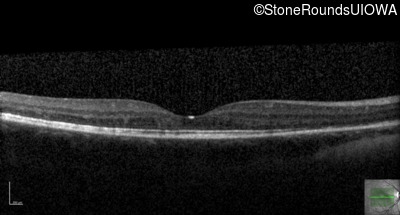

Optical Coherence Tomography - Left - 20/50 -2

Exemplar / OCT Stack